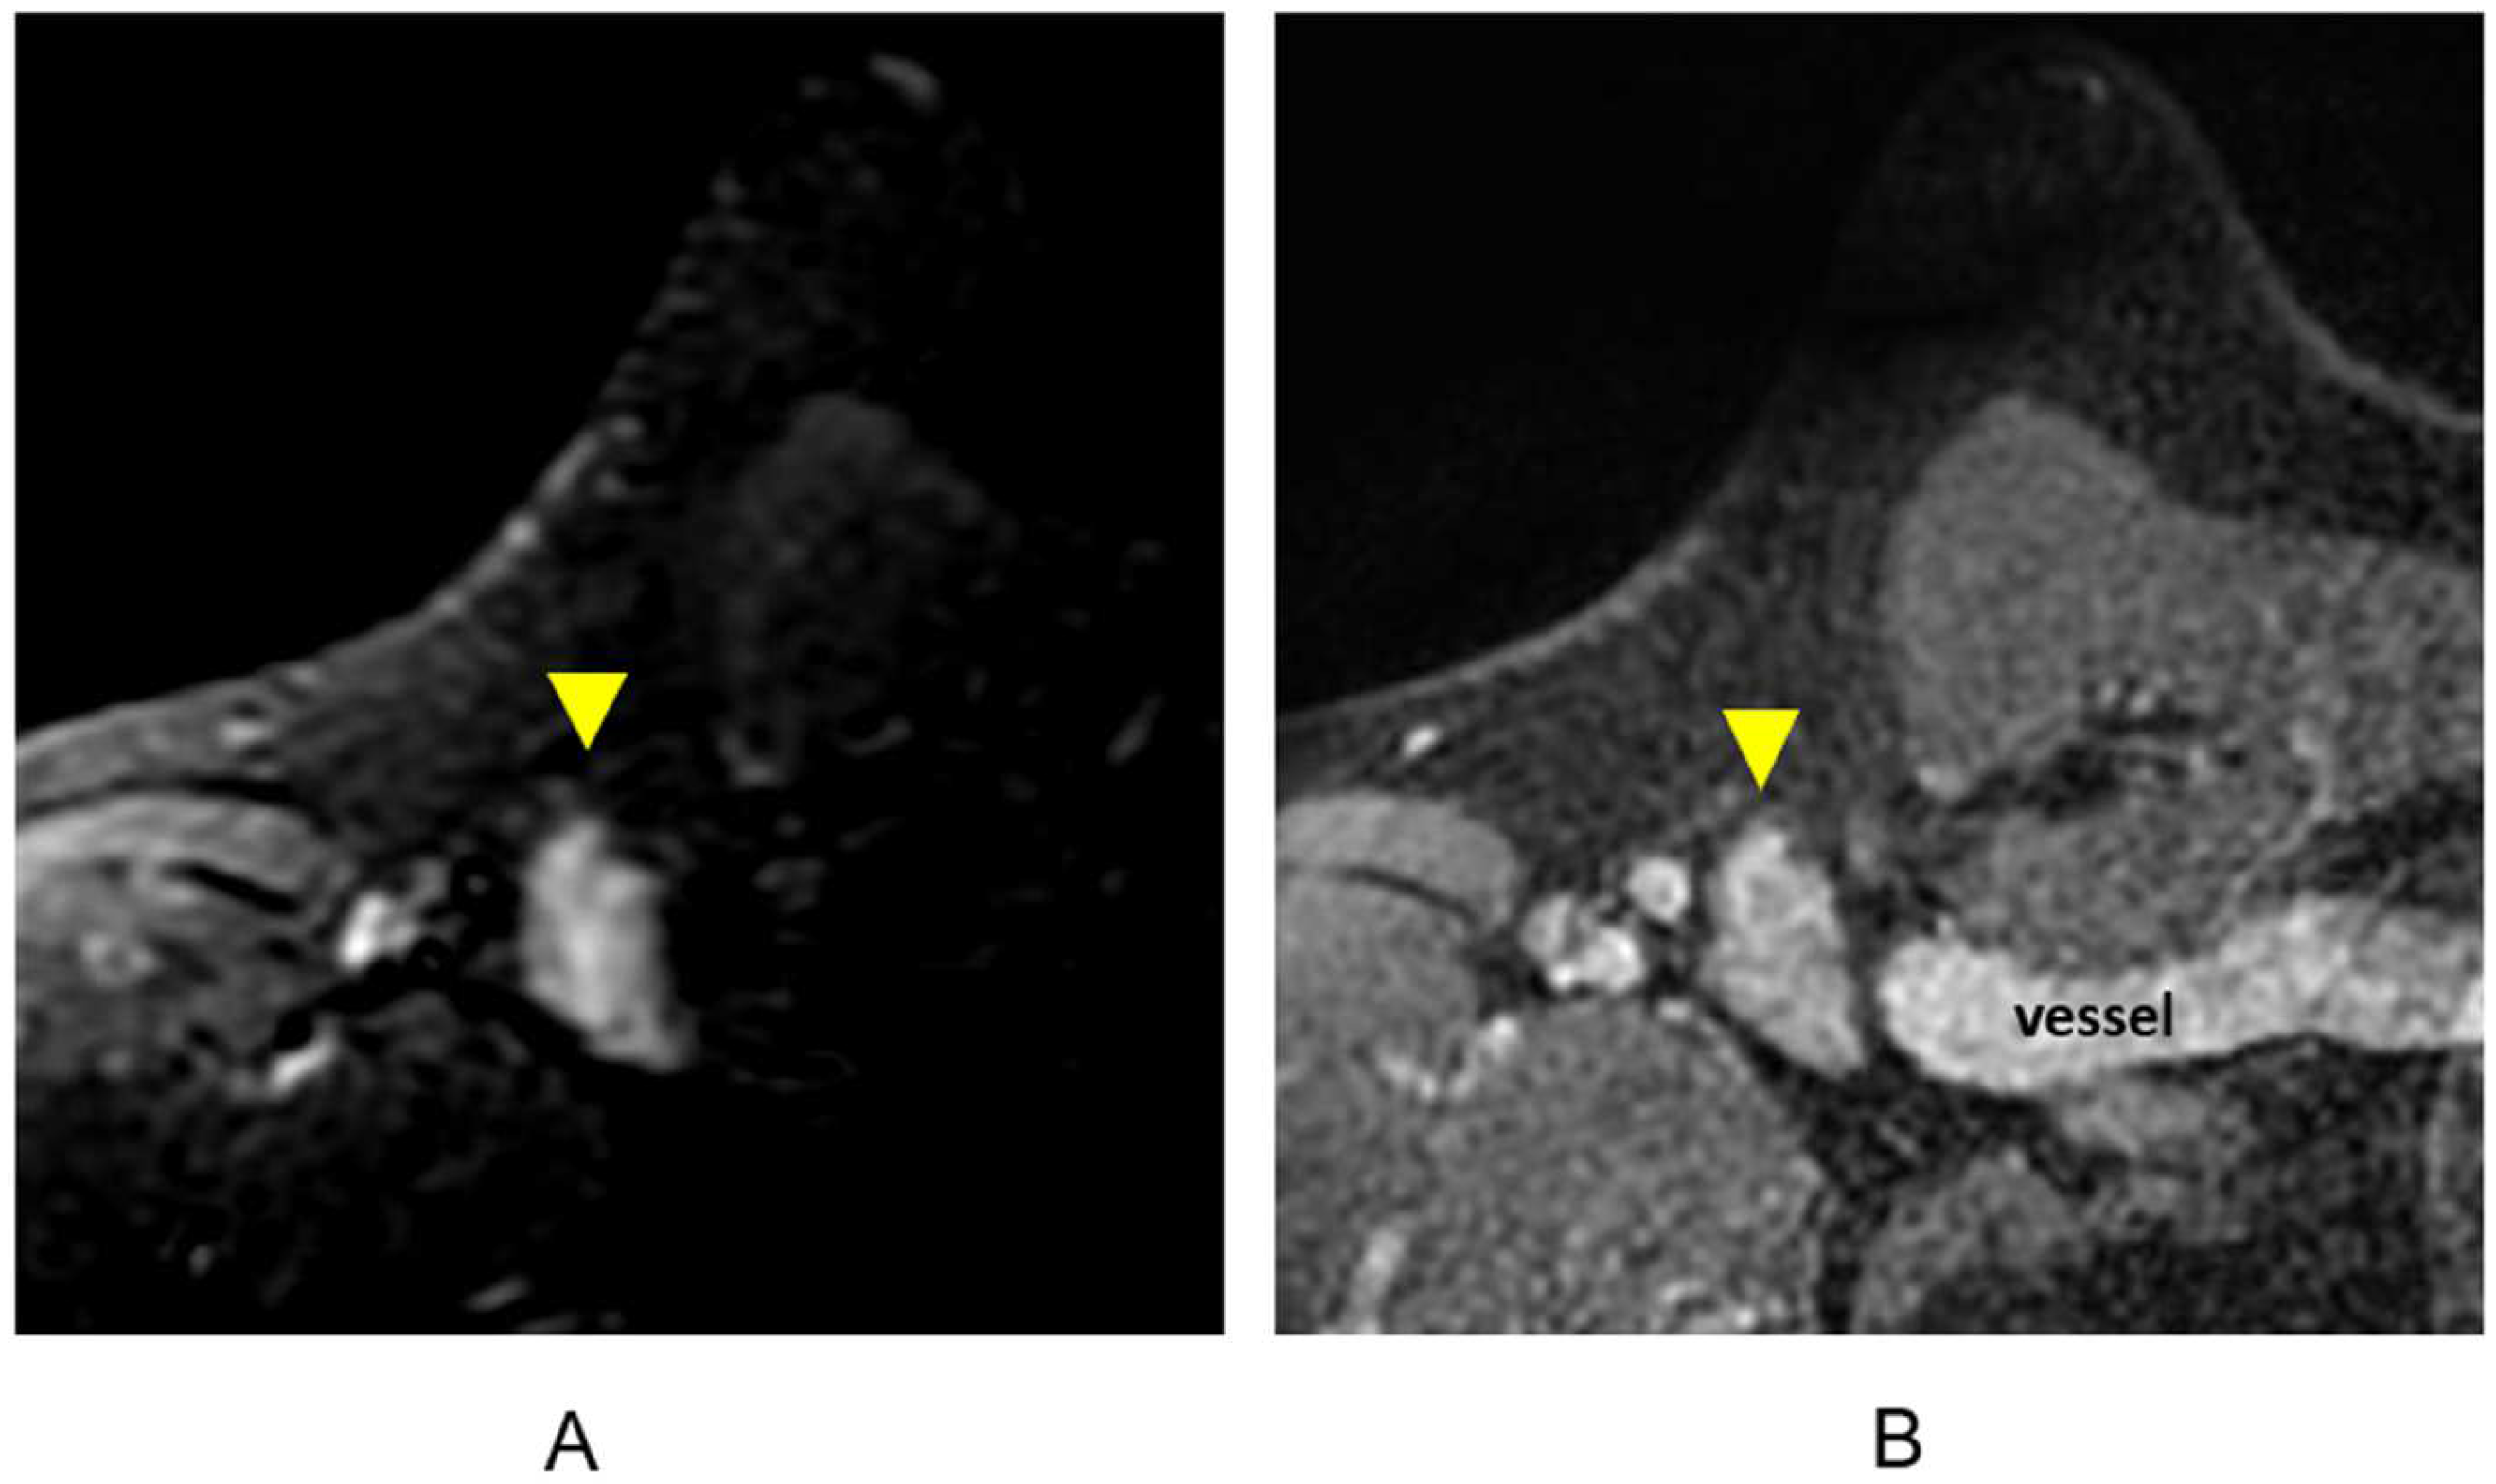

3.1.2. Evaluation of the Pectoralis Musculature, Chest Wall, and Nipple–Areolar Complex

3.1.3. Multifocal/Multicentric Disease